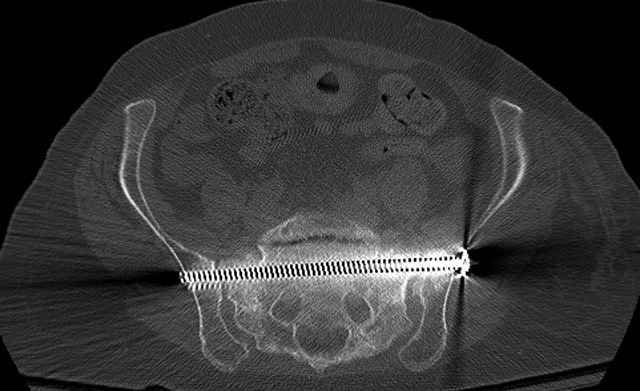

Percutaneous Fixation

(B) Ramus-Retrograde

2 TransIliac-TransSacral

Upper Segment

mlcr